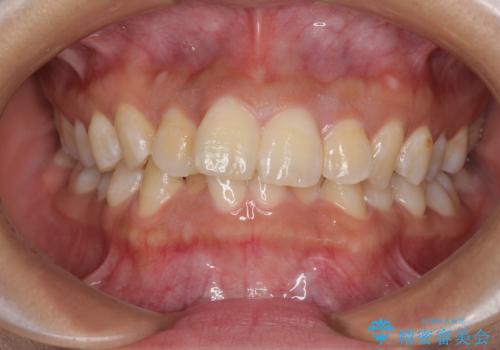

前歯のデコボコと隠れてしまう下顎前歯 インビザラインですっきりと改善

- 前歯のデコボコと、深い咬み合わせにより前歯が隠れていることを気にして来院された患者様です。

海外に長期滞在する予定があるとのことで、インビザラインにて矯正治療を行うこととしました。